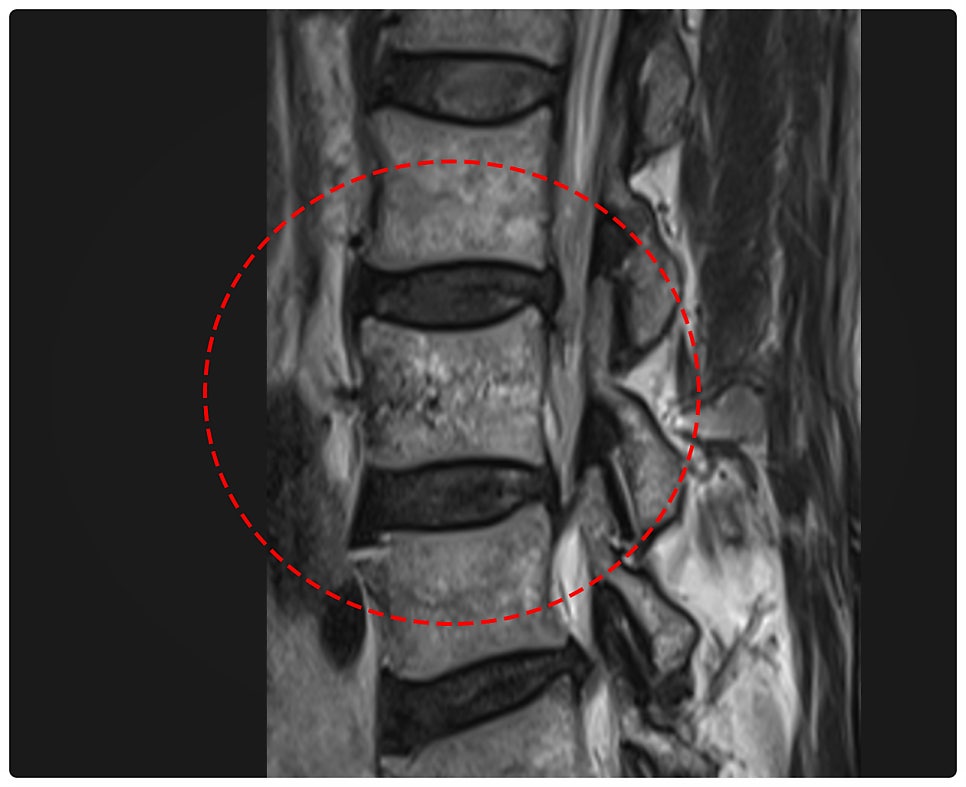

MRI 정밀 검사 영상을 얼핏 보면, 찌그러진 정도나 각도 변형을 알아보기 힘든 것처럼 보이는데요. 그래서 이번 사건의 경우, 보험사에서는 현재의 영상만을 기준으로 측정하여 장해를 인정하지 않으려고 할 것입니다.

만약 과거 영상이 없다면, 정상적인 생리적 후만 각도를 고려하지 않고 판단하여 부지급이나 축소 지급을 주장합니다. 사실, 이러한 측정 차이로 인해 큰 액수의 보상금이 차이가 날 수가 있으므로 신중한 청구가 필수적입니다.

고객의 의무기록을 검토하던 중, 과거의 기록에서 척추 영상을 발견할 수 있었는데요. 보통 사람이 지니고 있는 생리적 후만 각도가 확인되었고, 이를 토대로 현재의 변형된 각도를 측정할 수 있었습니다.

그리고 이러한 내용이 담긴 "후유장해 진단서"를 공신력 있는 제3의료 기관에서 발급받았습니다. AMA 평가 기준상, 후만 변형 각도는 약 16.5도로 측정되어 "척추의 뚜렷한 기형 (30%)"에 해당하였습니다. [아래 이미지 참조]